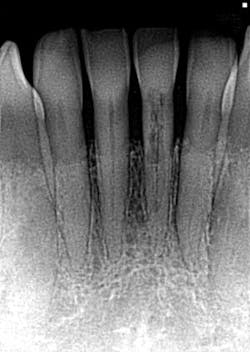

- In Figure 8, the lesion is advanced significantly (one-and-a-half years had gone by) the irregular borders and moth-eaten appearance is easily observed.

- Definitive diagnosis: external resorption.